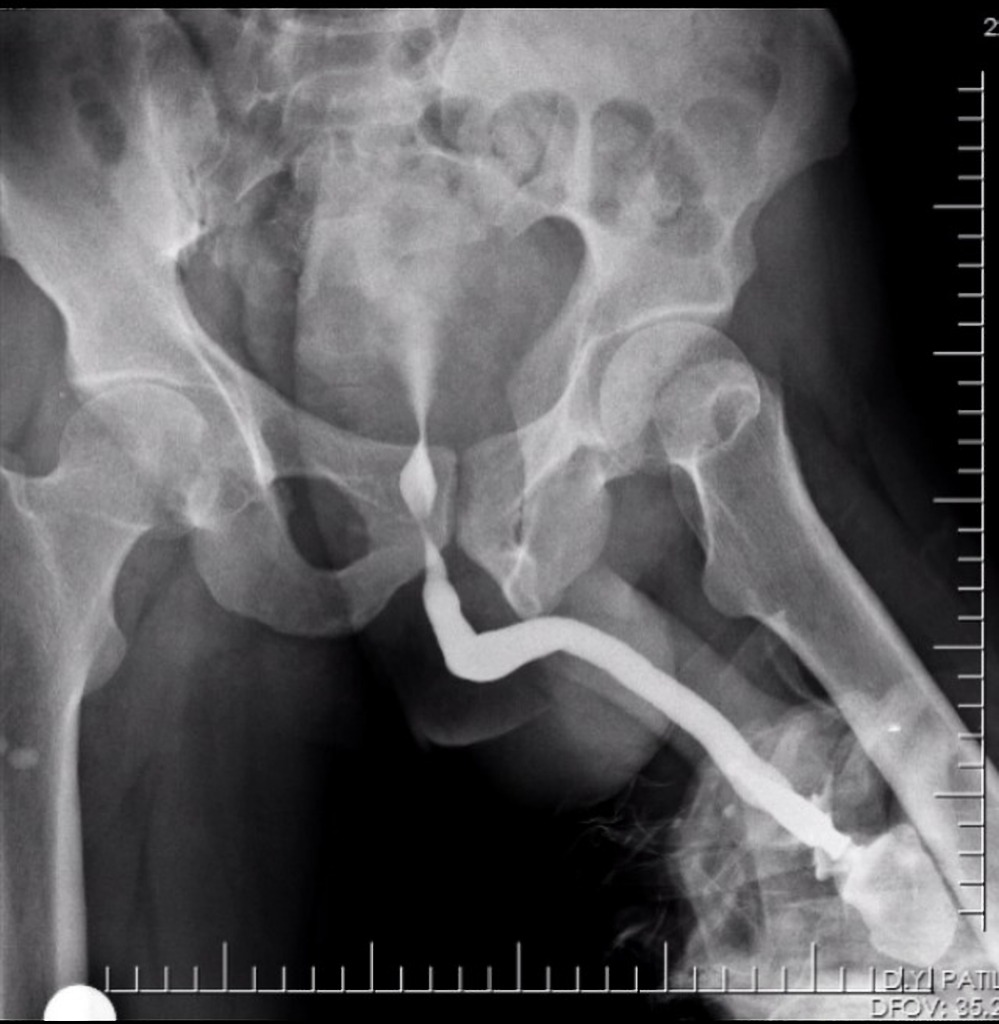

Retrograde Urethrogram . Under fluoro, insert the tip of the. Voiding cystourethrography (vcug), also known as a micturating cystourethrography (mcu), is a fluoroscopic study of the lower urinary tract in which.

Under fluoro, insert the tip of the. In posterior urethral strictures following blunt trauma, simultaneous.

Retrograde urethrogram showing bulbar urethral stricture (Case 2 , And you can ask the radiographer to email the report to your email id or you can collect hard copy.

Normal retrograde urethrogram (RUG) and voiding cystourethrogram (VCUG , Interrogate anatomy and integrity of anterior urethra.

Ultrasonographic and Retrograde Urethrographic Assessment of Aeti , Must perform before catheterization to prevent further urethral injury;